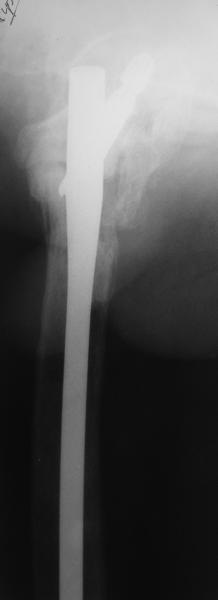

В приложении пример пациента, близкого по картине к тому, что

представил Виктор (варус и смещение периферического отломка на

поперечник кзади). Сделали как раз то, что Виктор исходно намеревался

- аппаратная коррекция и затем гамма.